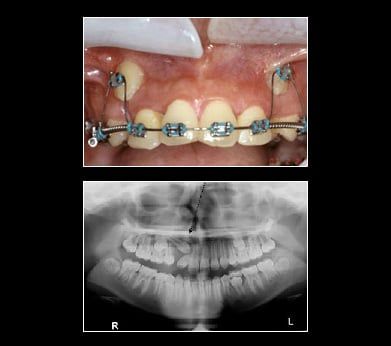

Impacted Canine